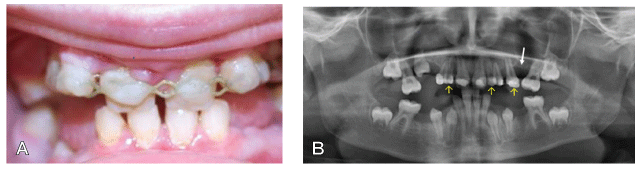

图1:十岁的女孩内部临床视图一见钟。

A.以中心闭塞的两个钳口的正面视图(清晰可见的DiaStema和Infrousted Molorars)。

B.上牙齿拱门牙齿的咬合视图。

C.矫形图(妊娠14,13,12,22,23,24,25,45)。

一个10岁的患者在象限II提到我们通过她的正畸医生进行咨询,由于在总(图1A-1C)与缺乏象限我三个恒牙的八颗牙齿发育不全,四个恒牙,一恒牙在象限IV,且不乏象限III。由于患者在在预约的时间年轻时是,主齿73和83仍然存在(图1C)。由于在上钳口(N = 7)的大量缺失牙齿的,我们决定于以下正畸手术的概念,它包括以下四个主要措施(图2):